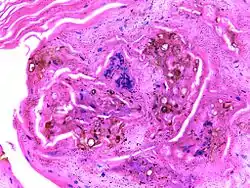

![]() Мікрографія препарату при хромомікозі, що демонструє вогнища склерозу Мікрографія препарату при хромомікозі, що демонструє вогнища склерозу | |

Хромомікоз (також Хромобластомікоз, англ. Chromoblastomycosis / Chromomycosis, також англ. Cladosporiosis, Fonseca's disease, Pedroso's disease, Phaeosporotrichosis, Verrucous dermatitis) — хронічна грибкова інфекція шкіри та підшкірної клітковини, яку спричинюють темнофарбовані патогенні гриби родини Dematiateae, представники якого широко поширені у довкіллі (ґрунт, гниюча деревина, солома тощо). Хворобу не слід плутати з мікозами, такими як міцетома або феогіфомікоз, спричинені іншими багатодомними грибами. Термін «хромомікоз» обмежений випадками, коли склеротичні клітини присутні в тканині. Склеротичні клітини, також відомі як тільця мушмули, мають глобусоподібну форму сигари, товстостінні структури діаметром 4-12 мкм.

Діагноз ставлять на підставі характерних клінічних проявів, мікроскопічного і /або культурального дослідження патологічного матеріалу (лусочок, гною). У складних діагностичних випадках необхідно проведення патоморфологічного дослідження. Діагноз підтверджується наявністю в досліджуваних субстратах (лусочки шкіри, гістологічні зрізи) тканинної форми гриба у вигляді так званих склеротичних клітин, «фумаго» або темних тілець, які являють собою округлі темно-пігментовані клітини з двоконтурною стінкою, що розділяються поперечною перетинкою на дві або три частини. Тканинні форми ніколи не брунькуються. При культивуванні лусочок, біоптатів на поживному середовищі Сабуро з'являється повільнозростаюча колонія (2–3 тижні) від оливково-зеленого до чорного відтінку.